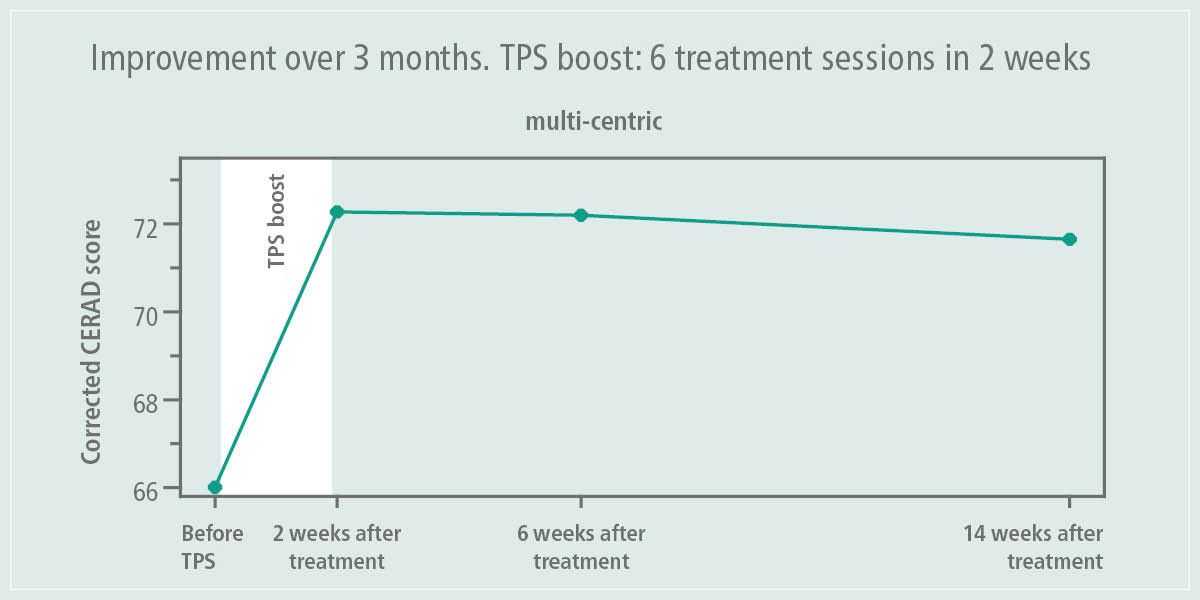

Shock waves are acoustic pulses that have been successfully used since the end of the 1980s to treat various clinical symptoms, such as extracorporeal treatment of kidney stones, diseases of the locomotor system, as well as pseudo-joints, to stimulate angiogenesis, in the case of abnormal wound healing and the treatment of angina. In the mid-1990s, the effectiveness of shock waves in neurological disorders such as post-traumatic contractions and spastic paralysis was recognized. In 2015, the first treatments were performed on patients with Alzheimer's disease at the University of Vienna. In 2018, transcranial impulse stimulation (TPS®) using the NEUROLITH® system received, as the only method of this kind, approval for the treatment of the central nervous system in patients with Alzheimer's disease. Other neurological conditions, such as Parkinson's disease, and psychiatric disorders, such as depression, are undergoing further clinical trials, research, and development.